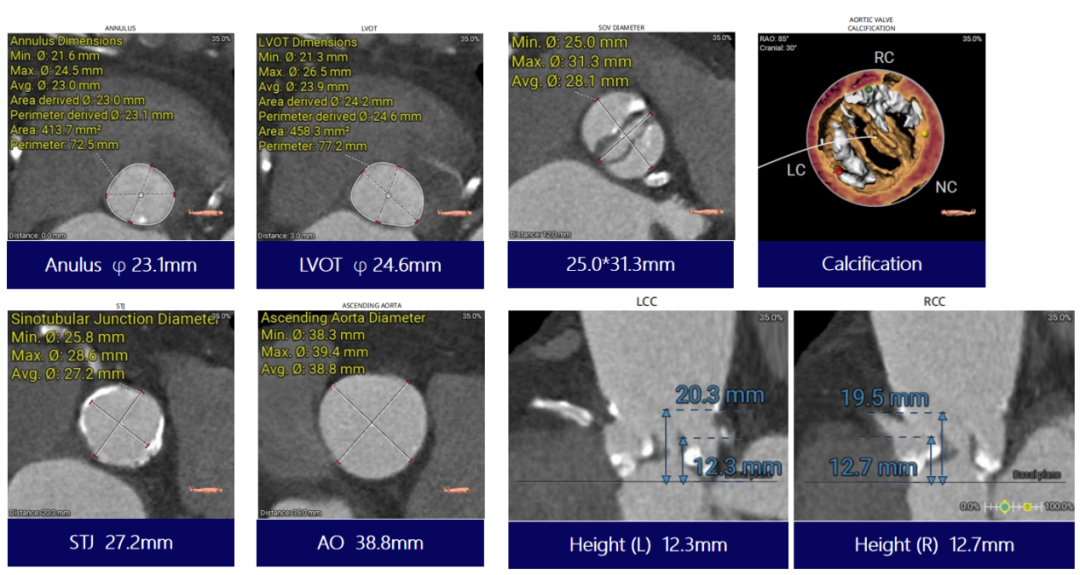

CT评估-基本测量:Type0型二叶瓣,瓣叶钙化较重并增厚,右冠瓣前交界处见团块钙化,瓣环直径23.1mm,流出道直径24.6mm

CT评估-环上多平面测量:环上较限制, 6-10mm处结构大小约21mm

冠脉风险评估:左右冠脉开口高度可,开口下缘见少许瓣叶结构,VTC测量>4mm,冠脉风险不高

CT评估-植入视图:双窦展开冠脉开口重合位

CT评估-左室测量:收缩期及舒张期左室内径可,舒张期瓣叶关闭良好